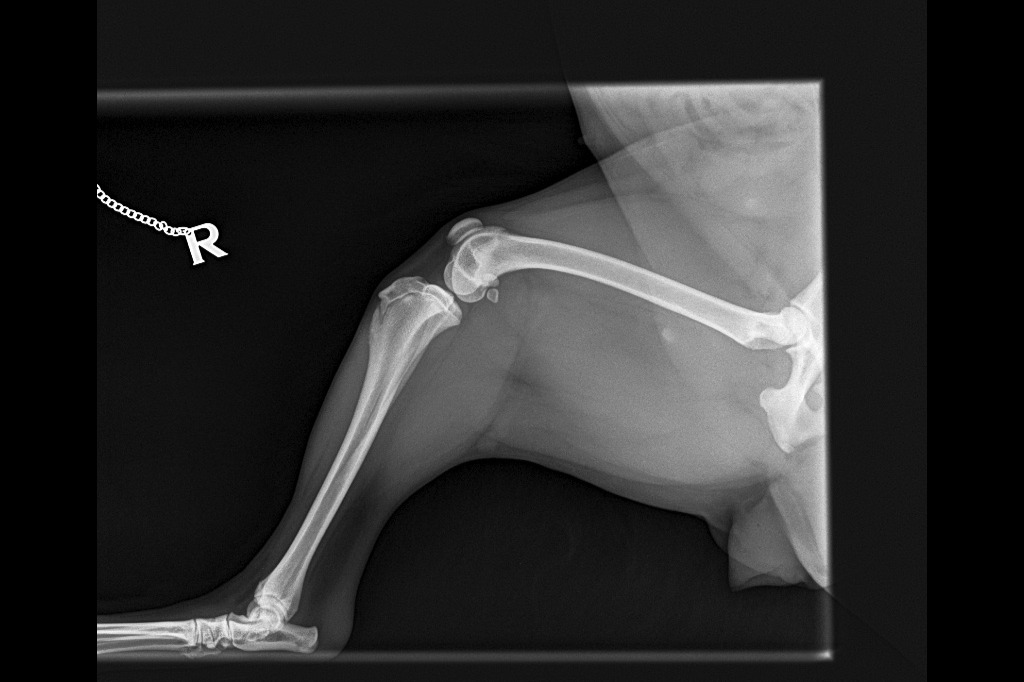

I can't walk anymore and the Vets said I have Luxating Patella issues and I need a surgery. I am scared to wee/poo because my legs would hurt if I flex/squat to wee/poo. My pictures below are the recent pictures after this incident and before the incident. If you want to see more pictures of me being lively and happy, please check my Instagram Profile lupe_gordita.